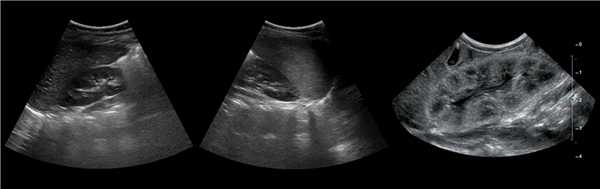

Рисунок. Дистальный отдел мочеточника расширен, в мочевом пузыре анэхогенное образование с тонким и ровным контуром — уретероцеле.